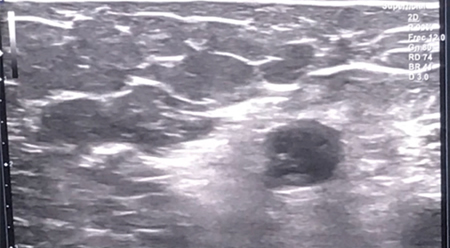

Figura 1

Figura 2

Figura 3